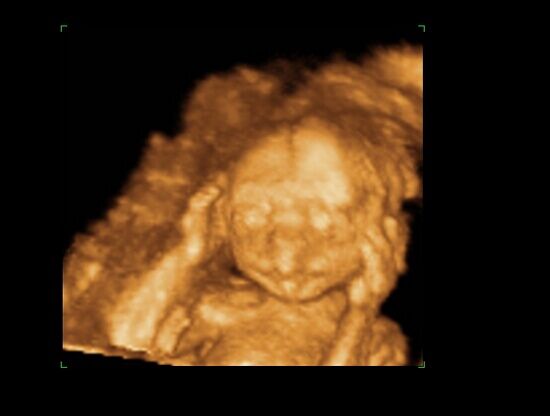

Huhh, hát annyira jó élmény volt, most tök boldog vagyok! Nagyon örülök, hogy mégis elmentem mégegyszer, mert sokat vacilláltam ám. A 4D Genesis egyszerűen szuper, mindenkinek nagyon nagyon tudom ajánlani, ezen belül is engem a Lengyel Györgyné Márti fogadott. Szuper ez a nő, akkora átéléssel és profizmussal csinálta az egész vizsgálatot! Mindent részletesen megnézett, megmutatott, elmagyarázott, nem sajnálta az időt. A felvétel gyönyörű lett, az egész baby nagyon szépen látszik, végig fent volt és mocorgott, hihetetlen aranyos volt, és nagyon szép!

Bemutatott párszor, ezek mind meg is vannak örökítve!

Na és a lényeg...jöjjenek a sztárfotók! Bocsi előre, 8 lesz és kicsit nagyok, de nem tudtam választani, azokat a bemutatásokat mind muszáj volt felraknom, tök vicces!